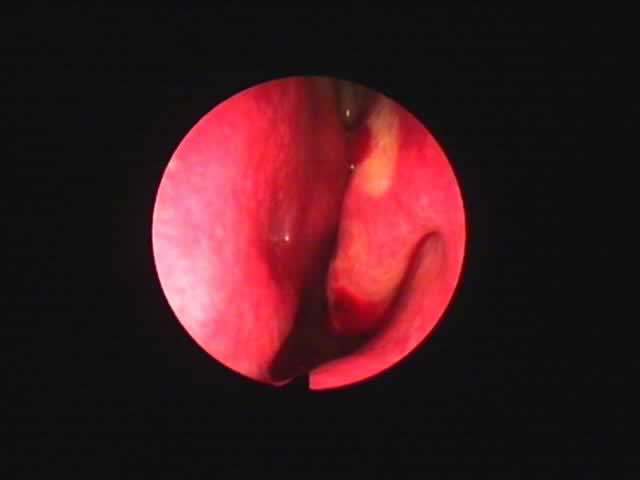

![]() |

| 7月16日 かなり縮小 | 両手術直後(縮小不十分なため追加焼灼、8月9日) | 9月8日 著明に縮小しいびき消失しているとのことです |